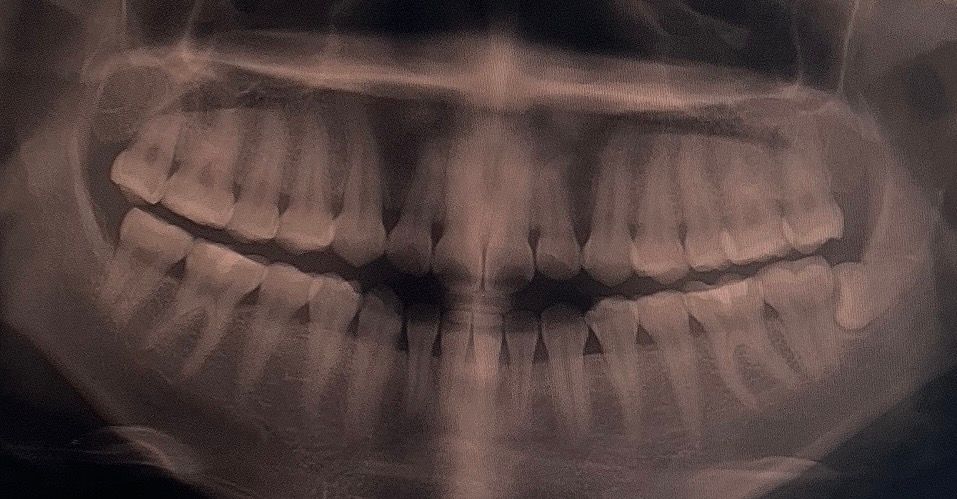

오른쪽 인접면 충치치료 진행상황 알러주세요

오른쪽 아래어금니쪽 인접면 충치가 있어서 인레이로 진행해야될 것 같다고 하셨습니다

(추가적으로 열어봤을때 너무 심하면 신경치료 고려해야한다고도 하셨습니다)

첫번째 사진은 최근 사진이고

두번째 사진은 처음 간 병원에서 찍은 사진입니다

(사진찍고 사랑니 발치 후 , 왼쪽 오른쪽 윗 어금니 • 왼쪽 아래어금니 레진치료 했습니다)

첫번째 사진에서 왼쪽 아래 뒤쪽 치아사이에 인접면 충치가 잇는거 같습니다. 치료를 하셔야될것같습니다.

오른쪽 아래 여섯 번째와 일곱 번째 어금니 사이에는 인접면 충치가 있는 것이 맞습니다. 인접면 충치가 있는 경우에는 레진으로 충전을 했을 경우 경계면을 만들어주기 힘들기 때문에 보통 인레이 치료를 하게 됩니다.